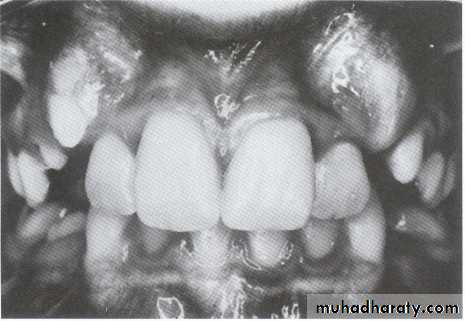

Crowding of teeth:

Defined as a lack of space for all teeth to fit normally with in the jaw.

disharmony in tooth to jaw size relationship.UNIVERSITY OF MOSUL

1- Maxillary – mandibular alveolar protrusion.UNIVERSITY OF MOSUL

COLLEGE OF DENTISTRY2- One permanent mandibular lateral incisor block out lingually and midline discrepancy.

4- One mandibular permanent lateral incisor block out labially and midline discrepancy.5- Bilateral exfoliation of primary mandibular canine.

8- Canine bulging in maxillary and mandibular vestibule.